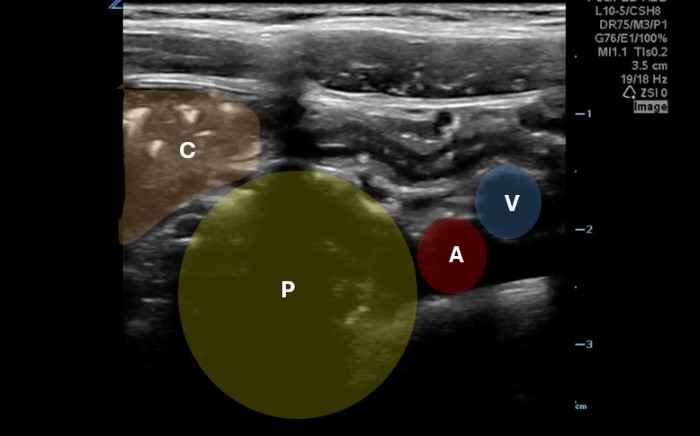

The linear probe is placed in the RLQ in the transverse position with indicator to the patient’s right. Identify the psoas muscle and iliac vessels lying medial. Once these structures are visualized, slide lateral and look superficially to identify the cecum. (Figures 1a,1b 1) Use graded compression-progressive increase and decrease of pressure to move any gas out of view. Keeping the lateral edge of the abdominal cavity in view (Figure 2), the ultrasound probe should slide cranial in traverse plane, visualizing the ascending colon until the hepatic flexure.  In this location, the colon turns just medial to the liver with the kidney deep in the view. (Figure 3) This is the most common location to identify ileocolic intussusception. If no tissue mass is identified, the probe should be turned to the sagittal plane with indicator toward the head (to keep the colon visualized in the transverse view) and moved across the transverse colon continuing to use graded compression to look for a tissue mass consistent with intussusception. Once at the splenic flexure (Figure 4), the probe should be transitioned back to the transverse orientation to interrogate the descending colon.

10-2024 Article7-1b.jpgFigure 1b. Right lower quadrant anatomy: A-iliac artery, B-iliac vein, P-psoas muscle, C-cecum of identifying landmarks of RLQ to identify cecum.